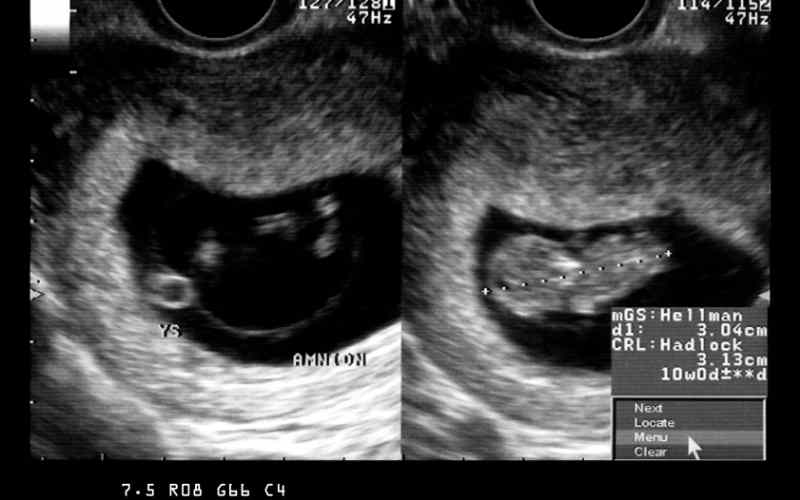

Vì vậy, đó chỉ là các dấu hiệu không có phôi thai xảy ra điển hình nhất, vẫn chưa đủ để xác định tình trạng sảy thai. Kết quả chính xác sẽ được phản ánh thông qua hình ảnh siêu âm thai cho thấy túi thai rỗng hoặc tử cung trống.